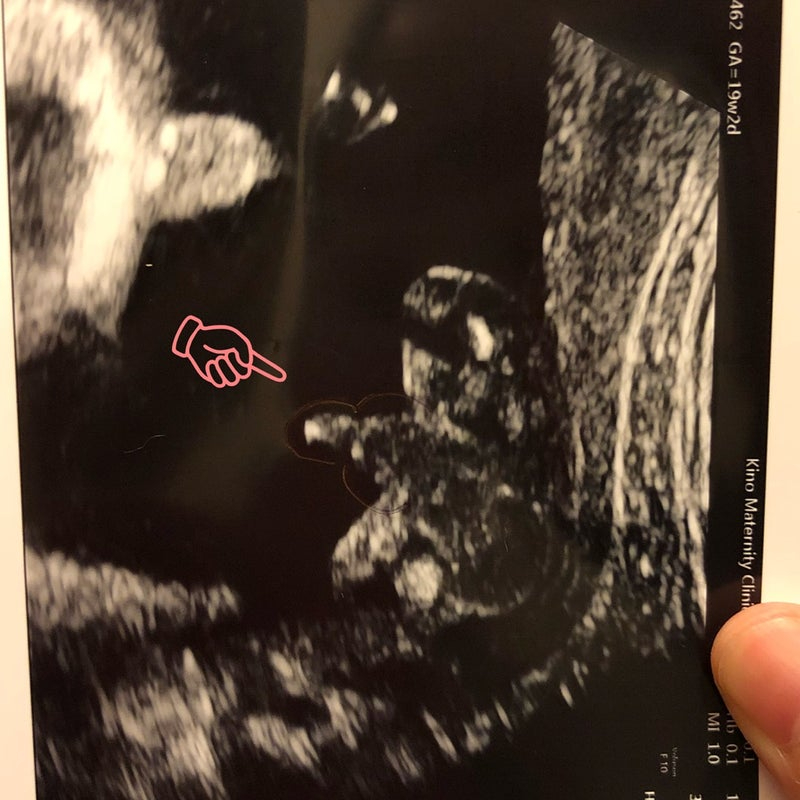

そして後のエコー検査では確かについておりました!

どうだ〜

IMG_8661.JPG

中川家のニューフェイス!

確かに男の子でございます✨